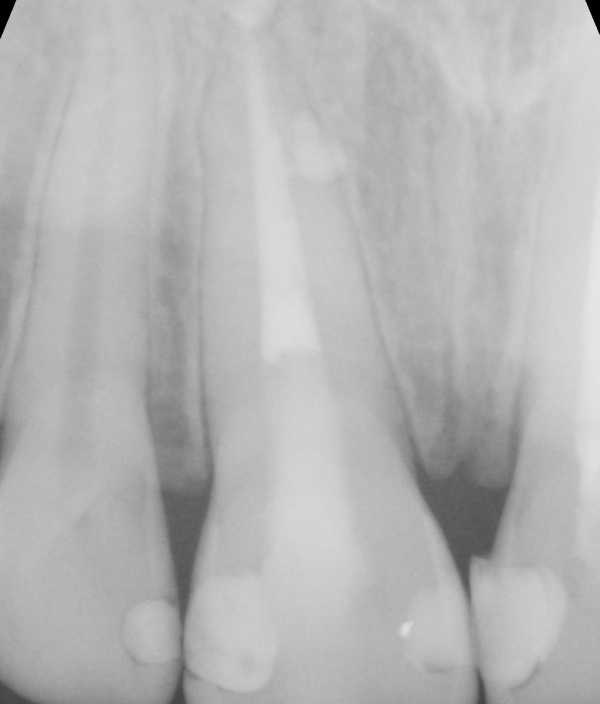

Kalcium silikátové materiály si od svého uvedení na trh získaly pověst vhodných materiálů pro zaplnění širokých kořenových kanálků nebo jiných situací v rámci endodontického ošetření, kde je materiál v kontaktu s nadměrnou vlhkostí.

Zároveň si však získaly pověst materiálů s obtížnou manipulací, což vedlo výrobce k vývoji předmíchaných kalcium silikátových sealerů. Tyto sealery nabízejí jednoduchou manipulaci, zejména při technice hydraulické kondenzace, kdy se zavádí pouze hlavní gutaperčový čep.

V určitých případech může být výhodná pístová technika. V rámci přednášky se dozvíte základní informace o kalcium silikátových materiálech – kdy je vhodné je využít, o kalcium silikátových sealerech – jaké existují, a také praktické informace o pístové technice – jak a kdy ji provést, jak si zjednodušit život a jak se vyhnout komplikacím.

Shrnutí kalcium silikátových sealerů a potřebného vybavení pro rychlé a efektivní zaplnění kořenových kanálků pomocí pístové techniky: